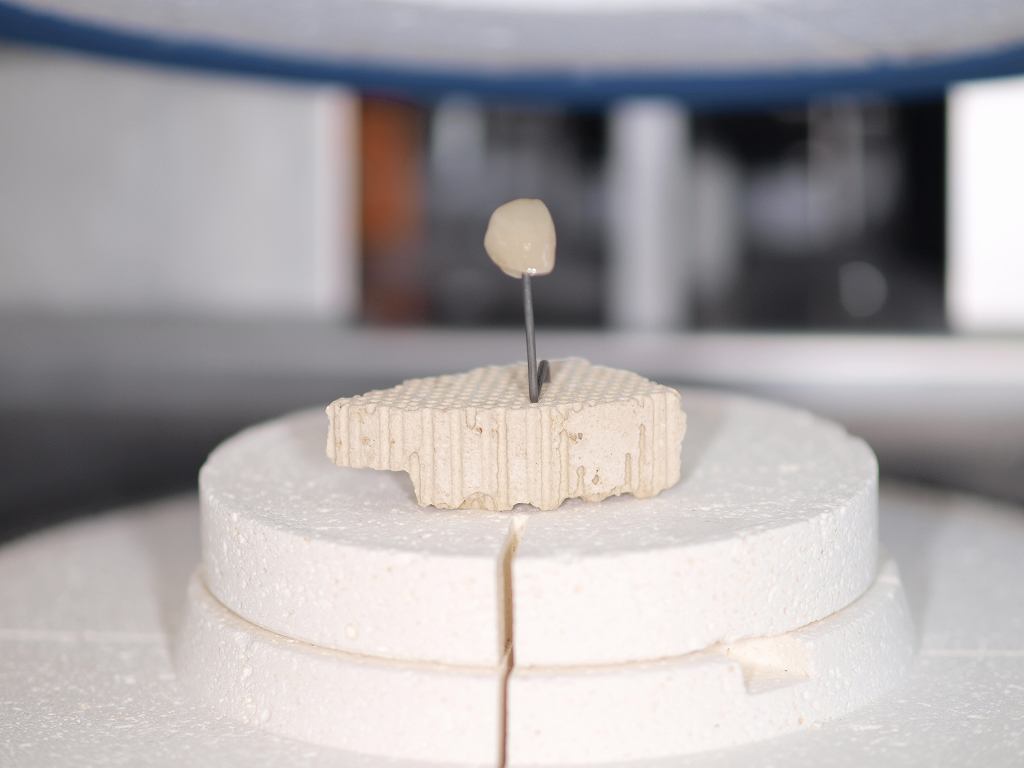

前歯部の作成はジルコニアフレームを使ったジルコニアクラウンというやり方とe-maxを使ったオールセラミッククラウンというやり方に分かれます。 強度はジルコニアフレームの方がありますが、複雑な工程を要しますので費用は2万円高く8万円となります。

前歯部の作成はジルコニアフレームを使ったジルコニアクラウンというやり方とe-maxを使ったオールセラミッククラウンというやり方に分かれます。 強度はジルコニアフレームの方がありますが、複雑な工程を要しますので費用は2万円高く8万円となります。